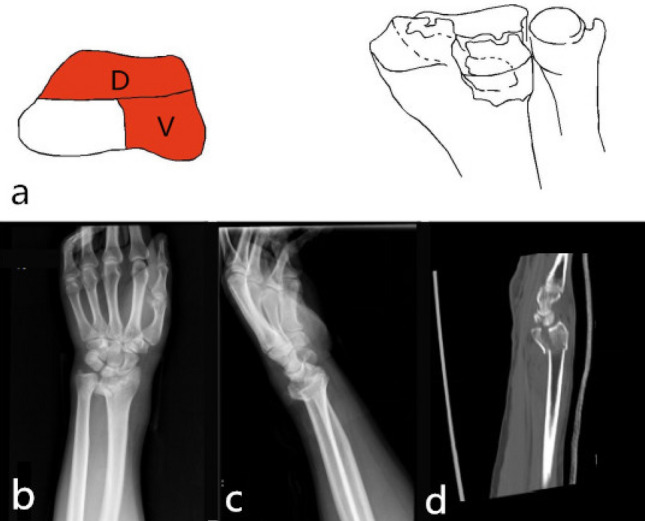

Dorsal part + palmar part (2-DV): The fracture was characterized by the separation of the lunar bone articular surface caused by the collision of the lunar bone with the lunar bone fossa, and the fracture line involved the sigmoid notch. Reconstruction of the sigmoid notch and check of TFCC stability was necessary during the operation. The injury mechanism was the axial violence of the lunar bone striking the lunar fossa. The surgical approach for reduction and fixation was the palmar approach, and the palmar plate was selected for fixation. There was a rotation deformity of the palmar part and the dorsal part on the deformed surface; it was often the counterclockwise rotation of the palmar part and the clockwise rotation of the dorsal part, which led to the narrowing of the joint surface of the radial wrist joint. Part of the flexion function was lost; it was necessary to correct the rotational deformity during surgery10,11 (9, 10) (Fig. 5).

Figure 5.

Distal radius fracture 123 classification B1.